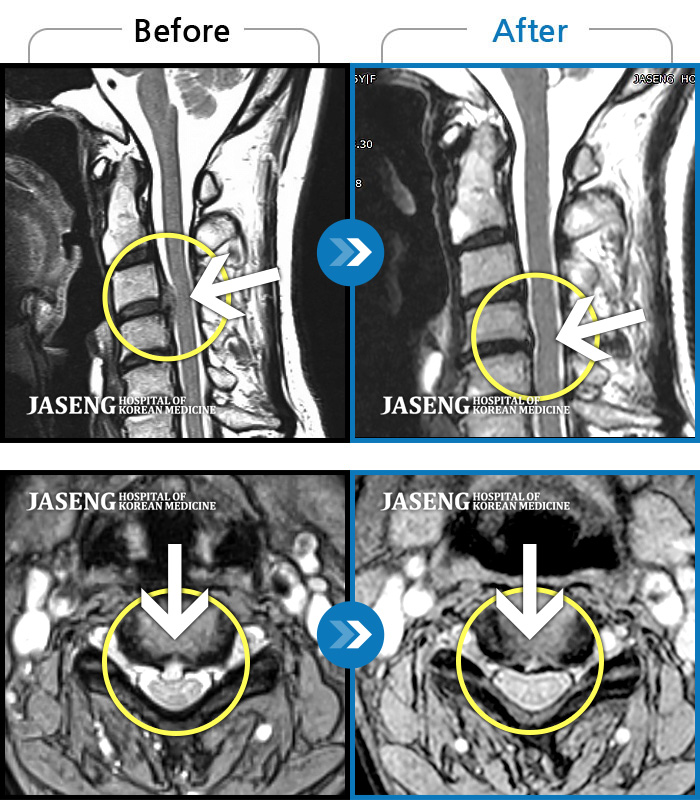

자생 비수술 한방통합치료 후

터진디스크가 흡수된 모습

Before

After

비수술 치료만으로

터진 디스크 흡수